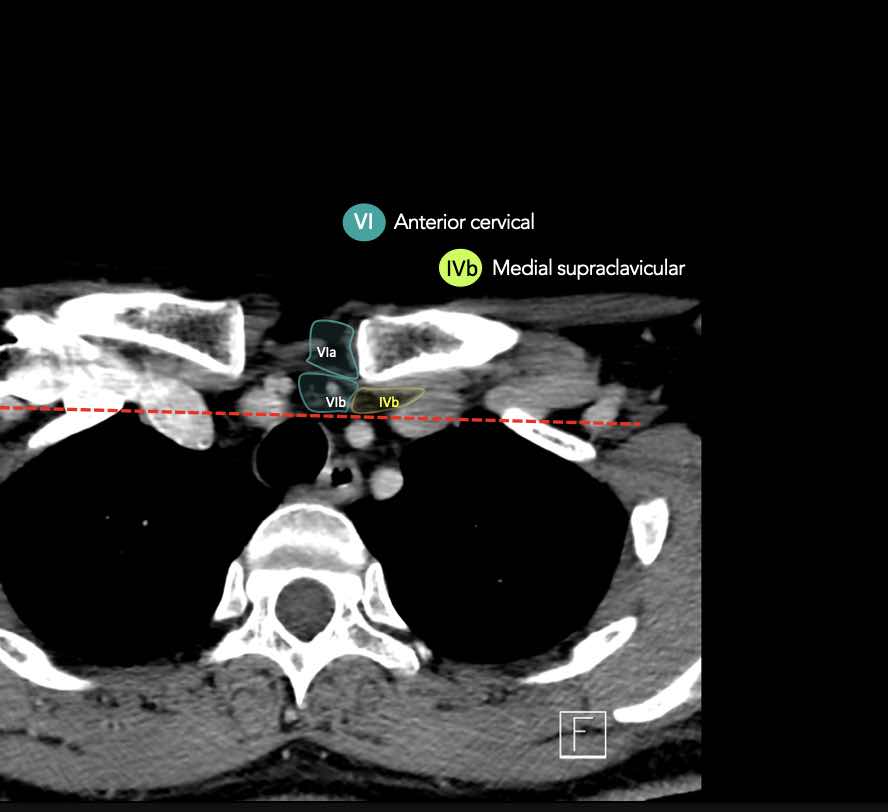

IV – Tĩnh mạch cảnh dưới và hố thượng đòn trong

Ranh giới giữa tầng IVa và IVb được xác định tùy ý tại vị trí 2 cm phía trên khớp ức đòn.

Tầng IVb

Các hạch này có nguy cơ chứa di căn từ các ung thư hạ hầu, thanh quản dưới thanh môn, khí quản, tuyến giáp và thực quản cổ.

VI – Cổ trước

Tầng này chứa các hạch tĩnh mạch cảnh trước nông (tầng VIa) và các hạch sâu hơn bao gồm hạch trước thanh quản, trước khí quản, cạnh khí quản và hạch thần kinh thanh quản quặt ngược (tầng VIb).